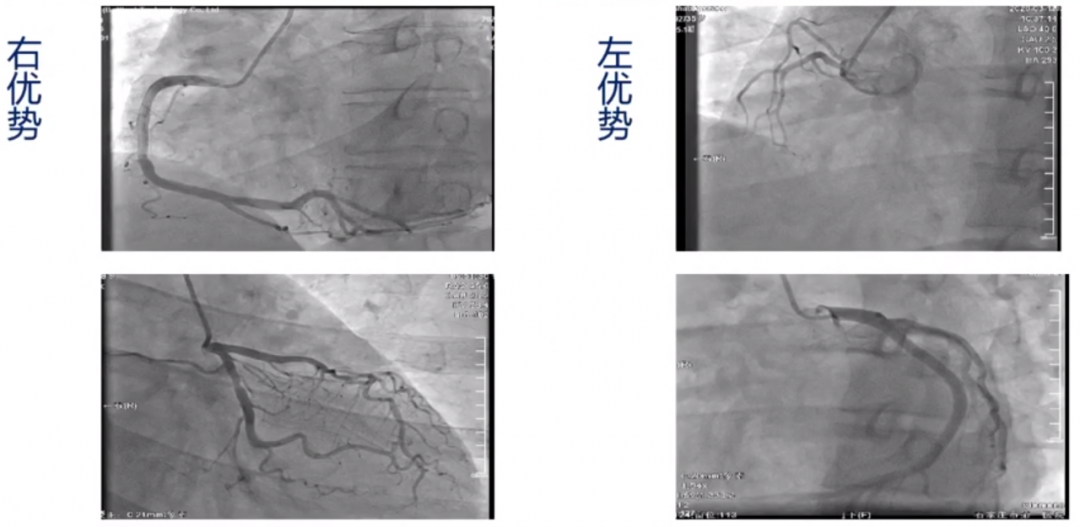

左右冠状动脉分布类型:

图4

图5